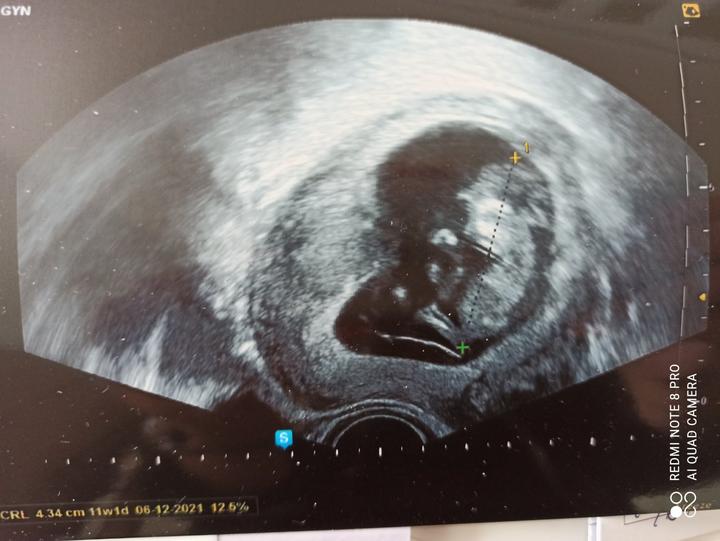

Dnes začínám 3.měsíc třetího těhotenství😁. V úterý odběry a kontrola, jestli ta naše malá larvička roste jak má, takový dlouhý víkend už jsem dlouho neměla. Nic mě nebaví a jsem protivná i sama sobě.